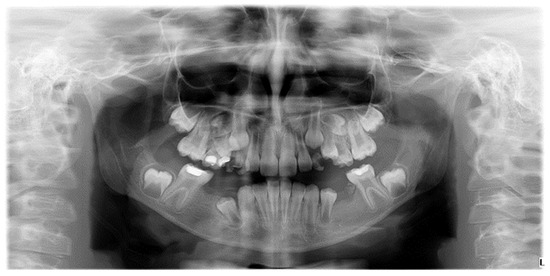

Figure 1.

Radiographic image of developmental dental anomalies (number, size, structure).

Confirming existing evidence regarding etiological links and exploring new, previously undetected associations is of particular importance, given that, to date, no studies have been conducted in Romania on the etiology of MIH in correlation with other coexisting anomalies to optimize treatment. The high prevalence of dental anomalies, especially hypodontia, in children with MIH is a new and clinically significant finding, requiring further research due to its potential implications for evaluation and treatment planning (Figure 3) [21].

Figure 3.

Radiographic image illustrating hypodontia in a patient with mixed dentition and clinical diagnosis of Molar-Incisor Hypomineralization.